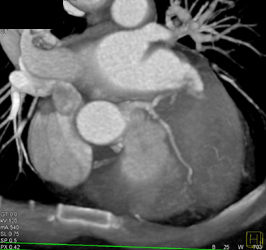

Diagnosis

Normal RCA